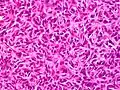

Subcutaneous tissue infiltration (i.e. "honeycomb" growth pattern)

Subcutaneous tissue infiltration (i.e. "honeycomb" growth pattern) Monotonous, plexiform structure of tumour

Monotonous, plexiform structure of tumour DFSP formed both by fibroblastic and histiocytic elements

DFSP formed both by fibroblastic and histiocytic elements Hemosiderin deposits beneath the tumour

Hemosiderin deposits beneath the tumour_CD34.JPG.webp) Immunostain positive for CD34

Immunostain positive for CD34